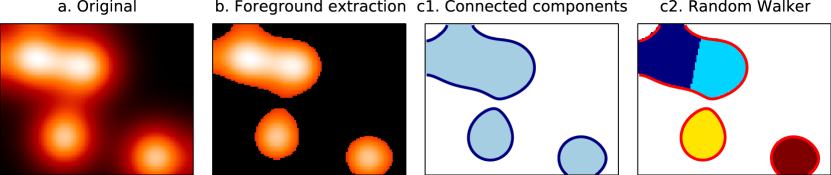

Extracting regions to outline objects is a well-known problem in computer vision. For the particular problem of extracting regions of interest (ROIs) out of brain maps, we want a method that i) handles 3D images ii) processes one image while taking into account the remainder of the atlas (e.g., region extraction for a given image may be different depending on the number of other regions) and iii) isolates each salient feature from a smooth image in an individual ROI without strong edges or structure (see figure 1). Here, we assume that a given set of brain maps has been obtained by a multivariate decomposition technique.

Connected components.

We define a connected component as a maximum set of foreground points that are -connected. The set of all -connected components for a given image (see figure 1.c1) is written . Extraction of connected components can be done after hard assignment or automatic thresholding to obtain ROIs (figures 2 and 4). In the following methods, we consider the points extracted with automatic thresholding as foreground () and use more sophisticated priors to extract ROI.

Random Walker.

Random Walker is a seed-based segmentation algorithm similar to watershed. It calculates, for each point , the probabilities to end up in each of the seeds by doing a random walk across the image starting from . The original version of the algorithm [4] was of probabilistic nature, whereby the probability to jump to a neighboring point is driven by the gradient magnitude between them. After convergence the point is attached to the seed with the highest probability.

Random Walker can also be seen as a diffusion process. It is equivalent to hysteresis thresholding where regions that have grown enough to share a boundary are not allowed to be merged. The probabilities to reach each of the seeds can be computed using the laplacian matrix of the graph associated with the map. Due to space limitations we refer the reader to [4] for the complete description of the algorithm. We suppose returns the seed associated with point . We refine our neighborhood relationship by considering two points as neighbours only if they are associated to the same seed:

Note that, in our setting, a high value in the map means a high confidence. So, instead of using the finite difference gradient, we consider the max of the image minus the lowest voxel. Therefore, diffusion is facilitated in areas of high confidence and more difficult elsewhere. We take the local maxima of the smoothed image as seeds for the algorithm.

Region shape

The regions extracted by hard assignment (figure 2.a) present salient angles and their limits do not follow a contour line of the original map. The straight lines are the results of two maps in competition with each other. The 1D cut shows that the threshold applied when using hard thresholding is not uniform on the whole image. The other methods look smoother and follow actual contour lines of the original map. On this particular example, automatic thresholding (figure 2.b) extracts 2 regions: a large one on the left and a very small one on the right. This is one of the drawbacks of thresholding: small regions can appear when their highest value is right above the threshold. Thanks to its high threshold, hysteresis thresholding (figure 2.c) gets rid of the spurious regions but still fails to separate the large region on the left. Random Walker (figure 2.d) manages to split the large region into two subregions.

Similarly, in figure 4 we can see that Random Walker manages to split the default mode network into 3 components, where other methods extract two.